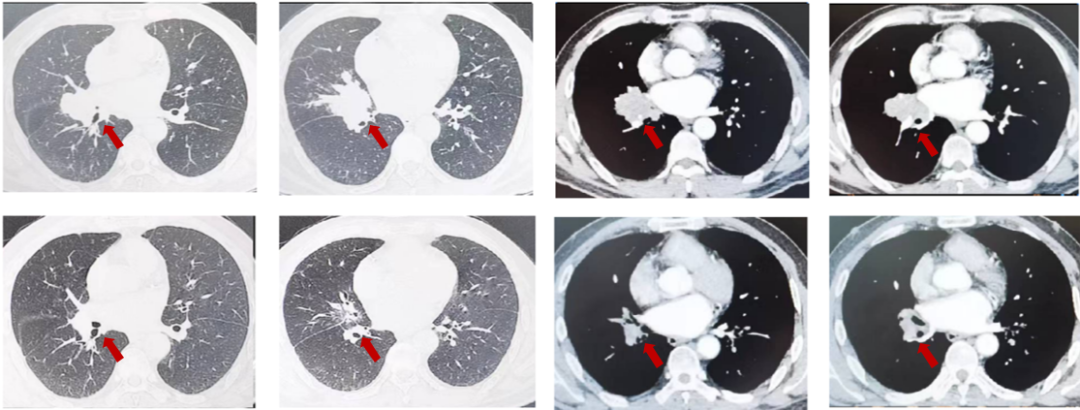

图3:由上至下分别展示基线(A.)及免疫化学治疗后改变(B.)。红色箭头指示病灶位置,由左至右分别为右肺肿物肺窗、右肺肿物纵隔窗。

图4:由左至右分别展示基线(A1-3)及免疫化学治疗后改变(B4-6)。支气管开口肿瘤明显退缩,结合影像判断达PR。